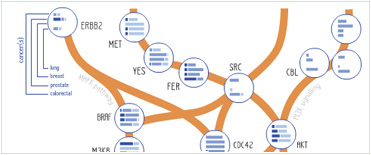

Foundational characteristics of cancer include proliferation, angiogenesis, migration, evasion of apoptosis, and cellular immortality. Find key markers for these cellular processes and antibodies to detect them.

Foundational characteristics of cancer include proliferation, angiogenesis, migration, evasion of apoptosis, and cellular immortality. Find key markers for these cellular processes and antibodies to detect them. The SUMOplot™ Analysis Program predicts and scores sumoylation sites in your protein. SUMOylation is a post-translational modification involved in various cellular processes, such as nuclear-cytosolic transport, transcriptional regulation, apoptosis, protein stability, response to stress, and progression through the cell cycle.